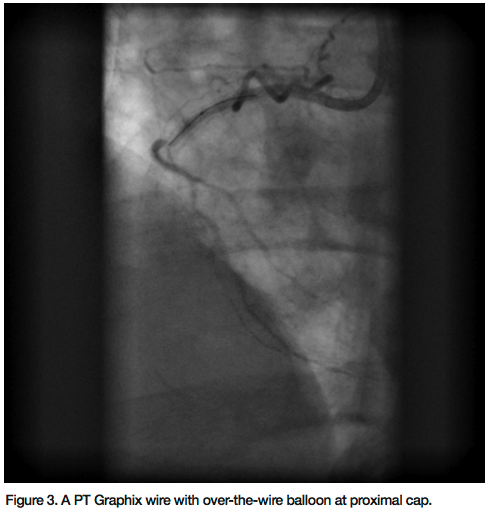

When he came to our hospital for a second opinion, a repeat catheterization showed a mid RCA in-stent chronic total occlusion (CTO) (Figure 1). The left system was free of any significant disease and septal collaterals filled the distal posterior descending artery (Figure 2). The left ventriculography revealed preserved systolic function with normal inferior wall motion.